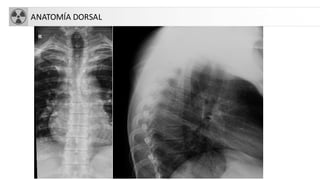

ANATOMÍA DORSAL

ANATOMÍA LUMBAR